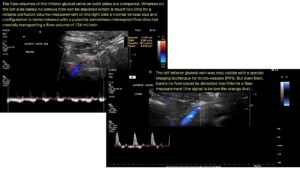

Die PixelFlux-Messung zeigt deutlich die Unzulänglichkeit der Kollateralgefäße der linken Nierenvene, während die Patientin in nüchternem Zustand liegend untersucht wird. Die Durchblutung der linken Niere beträgt dann nur 76 % derjenigen der rechten Niere.

Im Liegen nach dem Essen ist eine starke verminderung der Durchblutung in beiden Nieren erkennbar, wobei die linke Niere nur 20 % des stark reduzierten Blutflusses der rechten Niere erhält. Das Sitzen im nüchternen Zustand behindert den Blutfluss zur rechten Niere. Solch präzise Aussagen über hämodynamische Effekte und Blutflussverteilungsvolumina können nur mit der PixelFlux-Technik getroffen werden.